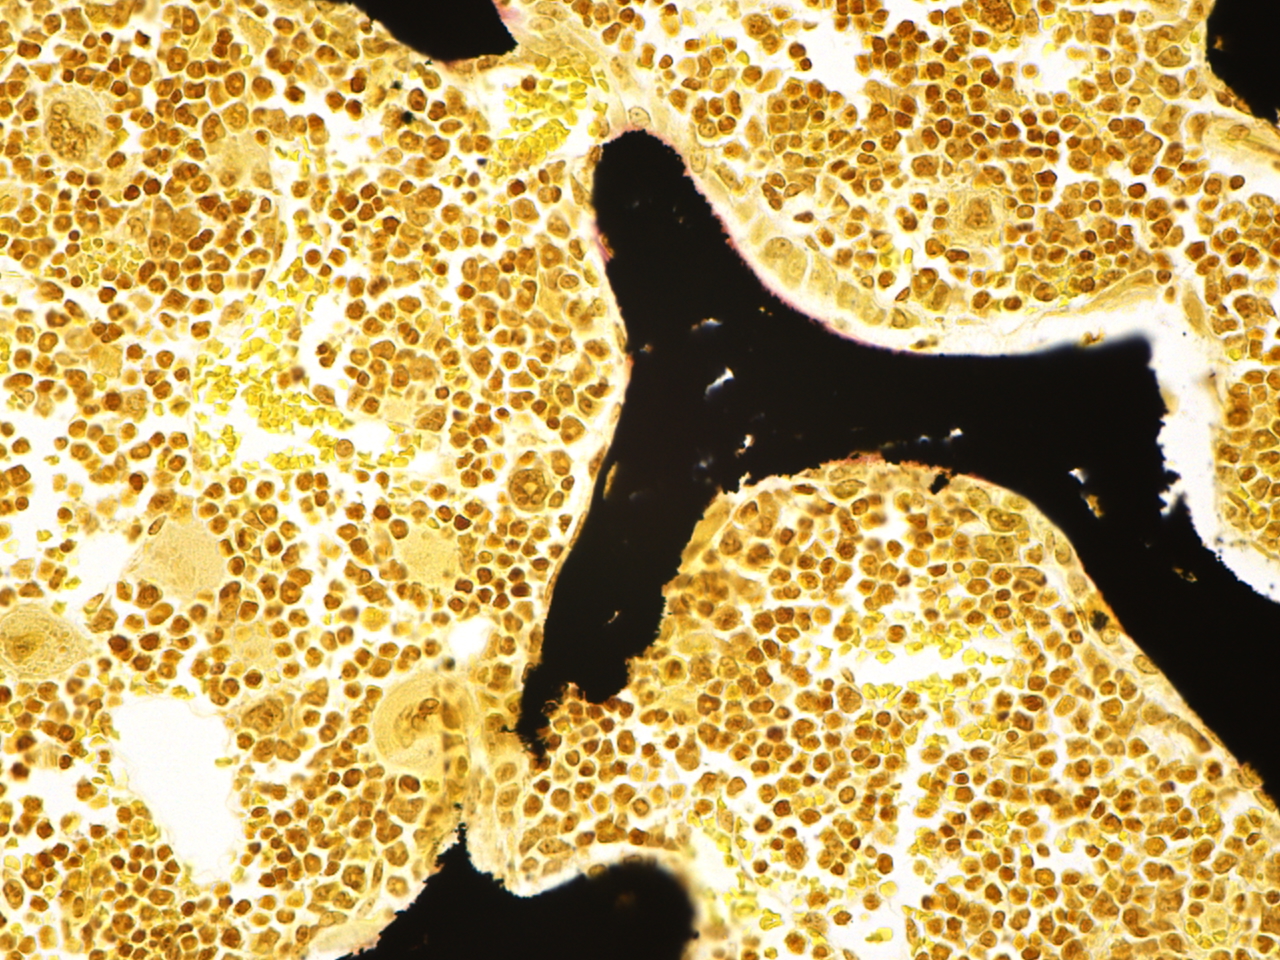

The MD Anderson Bone Histomorphometry Core Laboratory provides histomorphometric analyses of non-decalcified bone specimens. Bone specimens are processed for histology and can be stained for static and dynamic histomorphometric analyses (Osteomeasure or the Bioquant Osteo II system). The core can provides slides, data, training

Research Histology Core Lab: Bone Processing, Embedding and Sectioning

Bone Histomorphometry Core: Staining and Analysis